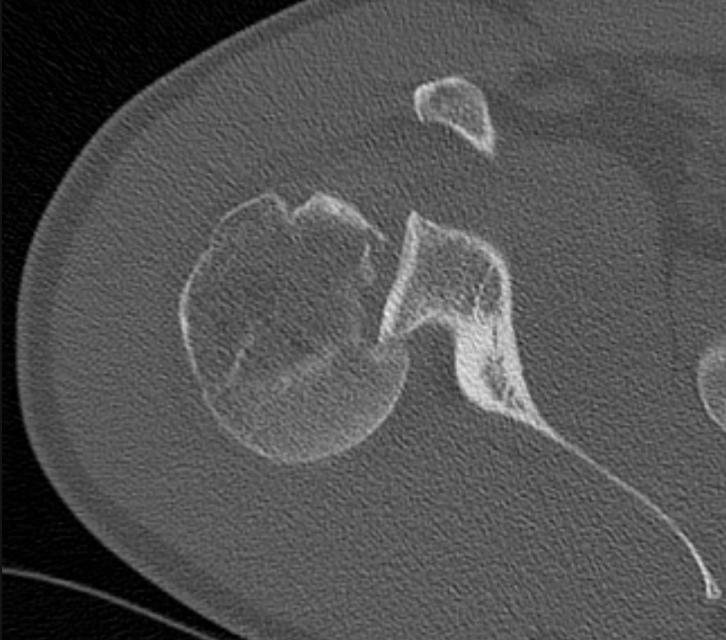

3. Reverse Hill Sachs lesion